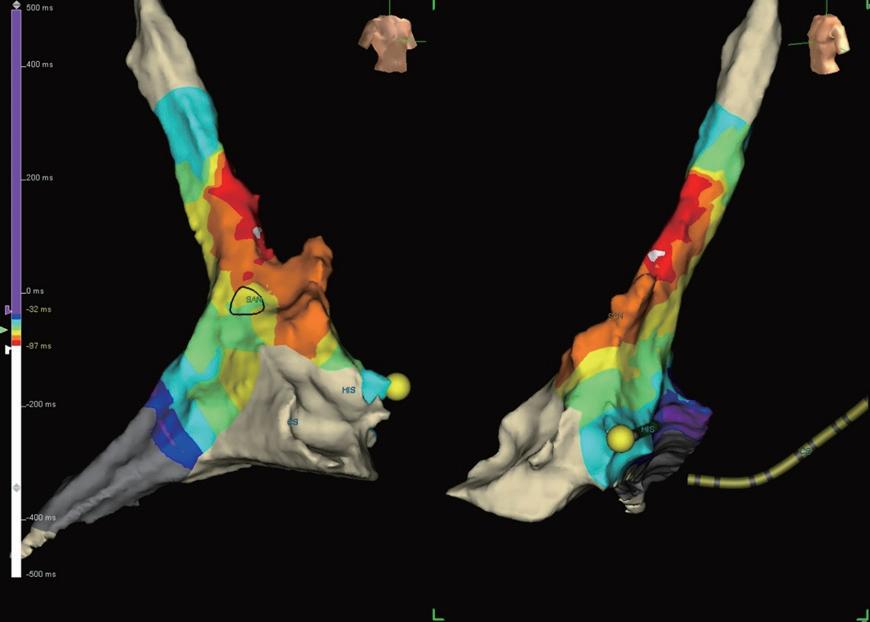

一位 50 歲女性, 6 年前開始有心悸的症狀。病患沒 有先天性心臟疾病。因為近日心悸頻發,所以來到門 診求診。做了 12 導程心電圖並沒有看到特別的異常 ( 圖 ) 。超音波檢查結果顯示心臟結構以及心室收縮率均 正常。Event recorder則是檢測出short RP tachycardia, 心跳介於 120 到 150bpm( 圖二 ) 。經解釋後病患希望接受 心導管電生理檢查並電燒處理。診斷管放置位置如 ( 圖 三 ) , retrograde 傳導測試發現 VA 傳導功能差, RVS1S1 無法達到VA 1 to 1,VERP則是250ms。Anterograde傳 導測試發現dual AV conductive property;fast AV 1 to 1

是 750ms , slow AV 1 to 1 為 500ms , AV fast ERP 為 680ms , AV slow 1 ERP 為 320ms , AV slow 2 ERP 為 300ms 。 pacing 誘發測試無法誘發 tachycardia ,所以我

們加上 isuprel 併作誘發測試。但加上 isuprel 後 VA 傳導

功能仍然不佳,而且也仍然無法誘發 tachycardia 。 於是加上了 atropine 測試;加了 atropine 後 long RP tachycardia 被誘發,速度為到 120-140bpm 和臨床表現 相符。此時V pacing仍然顯示VA dissociation,A pacing可 知delta AH為6,且比較心電圖可見SR時II、aVL為+, III 、 V1 為 +/- , tachycardia 時 II 、 III 為 + , aVL 為 flat , V1為+(圖四)。由以上特徵推測為atrial tachycardia(AT)。 因此使用 3D 定位找出 AT 最早的位置在上腔靜脈 (SVC) 的 anteroseptal area( 圖五 ) 。在使用 RF 45W 50C 160 seconds 後, AT 便無法誘發,術後也未曾復發。最後的 診斷為 anterosetpal SVC atrial tachycardia with slow pathway ;由於患者發作的時候, anterograde 傳導跳到 了 slow pathway ,所以 event recorder 的心電圖表現為 short RP tachycardia。

(圖四) 左側為tachycardia,右側為SR

(圖五) AT發作的位置如白色點所示,黑色圈為sinus node